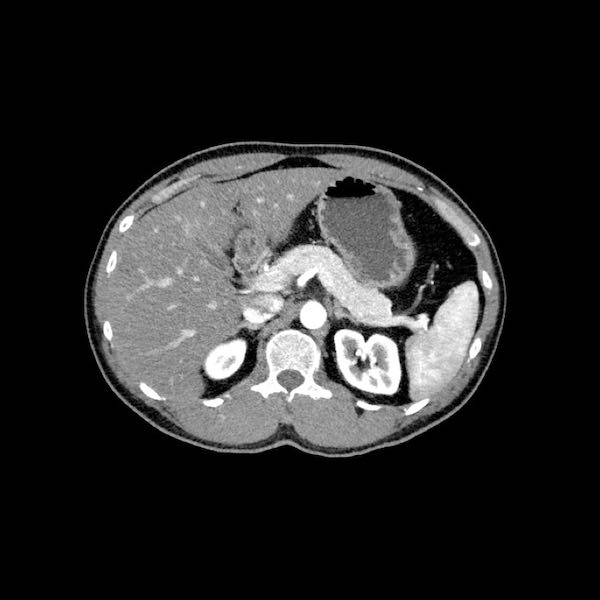

Đánh giá giai đoạn tại chỗ cần được thực hiện bằng CT tụy chất lượng cao, bao gồm thì động mạch muộn và thì tĩnh mạch cửa.

Ung thư biểu mô tuyến tụy thường biểu hiện là một khối giảm tỷ trọng, kém mạch máu, được nhận thấy rõ nhất ở thì động mạch muộn. Đây cũng là thì tốt nhất để đánh giá giải phẫu động mạch nhằm phát hiện các biến thể và hẹp mạch.

Thì tĩnh mạch cửa là tốt nhất để phát hiện di căn gan cũng như phát hiện hẹp và xâm lấn tĩnh mạch.